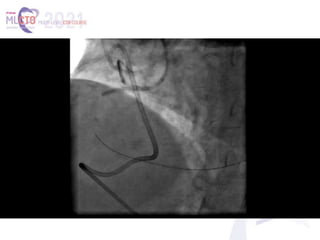

(A, B) The proximal right coronary artery (RCA) occlusion, visualized with separate antegrade and retrograde contrast

injections. Side branch–like, tortuous, continuous transseptal collaterals from the left anterior descending coronary

artery (LAD) supply the distal RCA (white arrow). Notice the mid-LAD severe focal stenosis (yellow arrow). (C) Lesion was

assumingly crossed by antegrade wire escalation, facilitated by proximal anchor technique. Notice the guidewire course

mimicking the imaginary contour of the native RCA artery. Crossing was not confirmed by contralateral injection, and 2

compliant balloons were inflated to dilate the lesion (white arrow). (D) Ellis type III coronary perforation into the

pericardial space (red arrow). (E) Delivery of the microcatheter to the distal cap (white arrow), following proximal

balloon inflation and placement of a pigtail pericardiocentesis catheter. Notice the ectopic guidewire into the

pericardium (red arrows). (F) Wire system externalization through the crossed lesion and the transiently deflated

proximal balloon (white arrow). (G, H) Final result. Sealing by deploying 2 drug-eluting stents, overlapping at the area of

the perforation. The mid-LAD lesion was treated with a drug-eluting stent with a similarly excellent result.